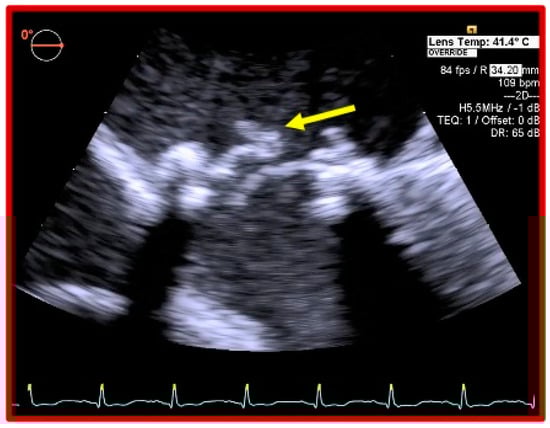

Early Basal Cuspal Tear of a Porcine Bioprosthetic Mitral Valve Causing Massive Mitral Regurgitation